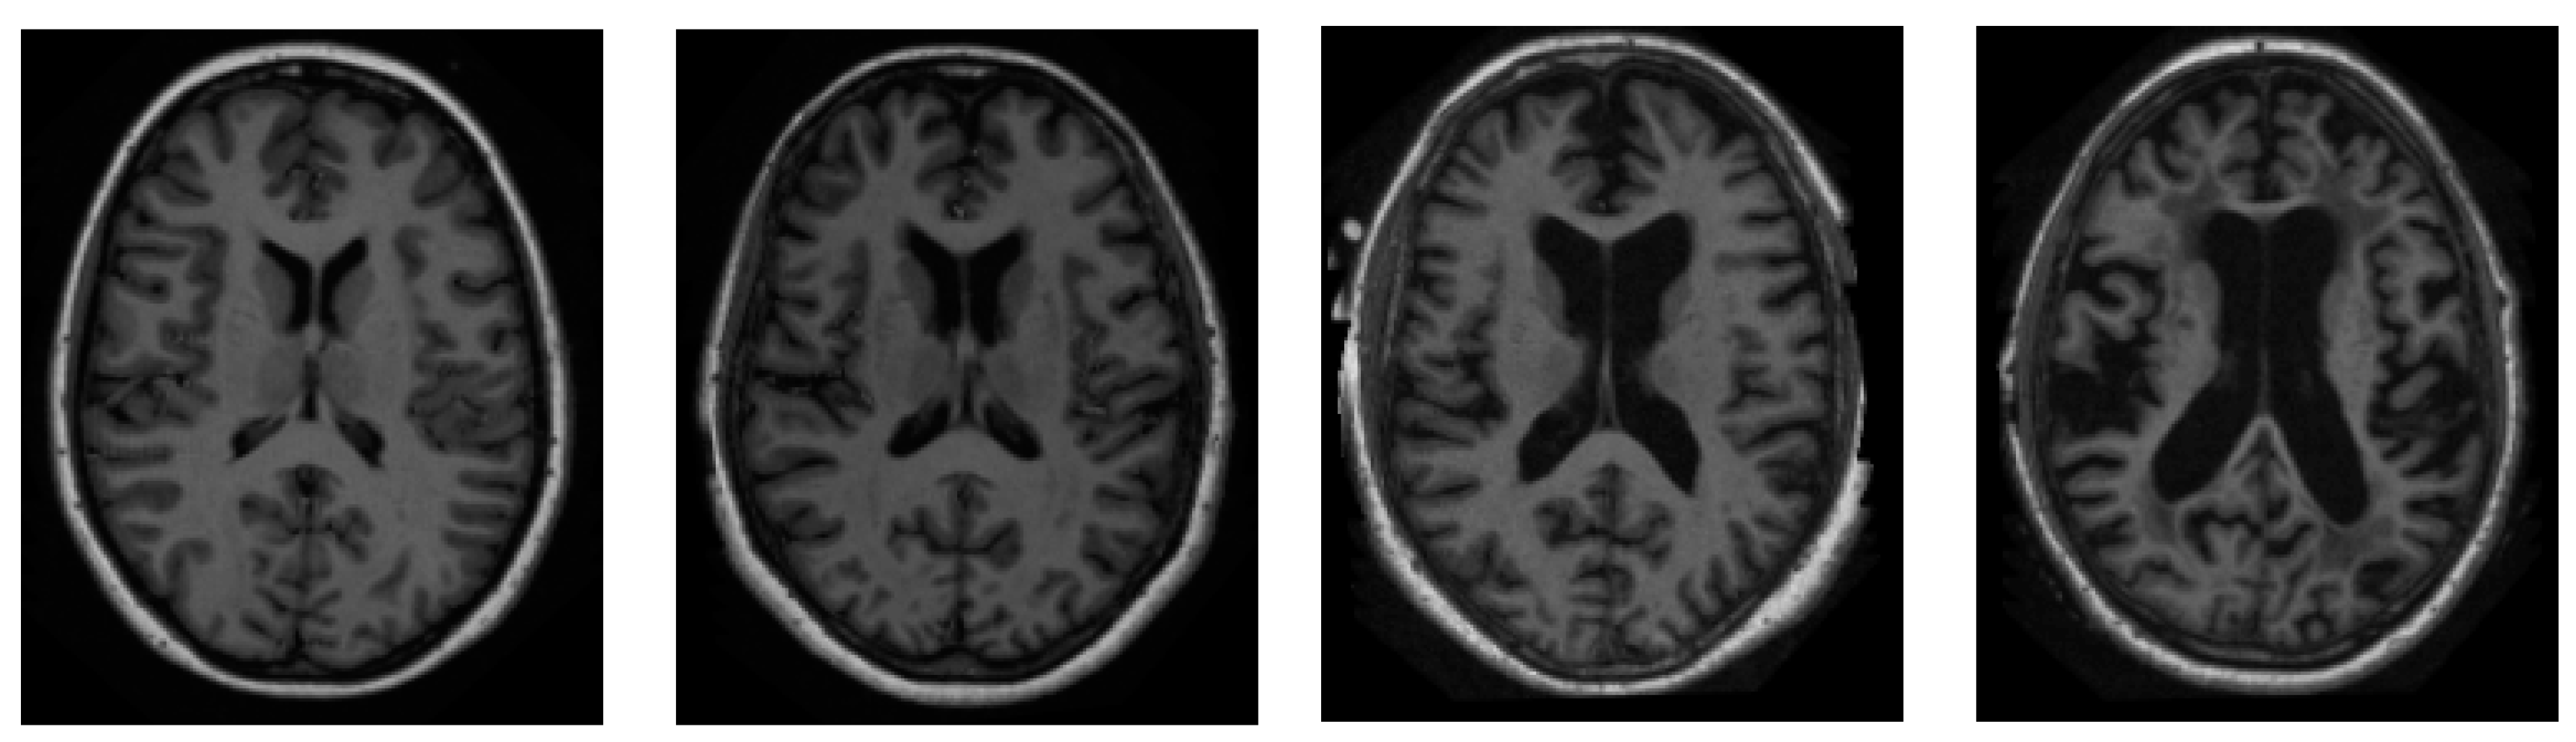

We sourced all of our information from the ADNI dataset [46]. ADNI is an invaluable resource for researchers [47]. A total of 416 people were included in this cross-sectional dataset. The ages of these participants range from 18 to 96 years. Three or four independent T1-weighted MRI scans are acquired in a single session for each subject. The sample images from the ADNI dataset have been presented in Figure 2.

Figure 2.

Sample pictures of an AD patient from the ADNI dataset.

Both sexes are represented, and everyone is dominantly right-handed. From very mild to moderate AD, 100 of the 416 subjects aged 60+ have been diagnosed. A reliability data set, with images from the follow-up appointment within 90 days, is also included for 20 people without dementia.